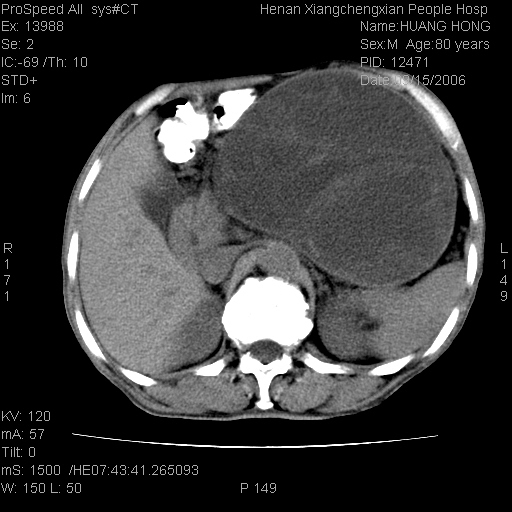

患者, 男, 80岁, 发现上腹部包块1年余,无其它不适.2006-9-14ct片是喝水后扫描2006-9-15ct片没喝水扫描![]() ![]() ![]() ![]() ![]() ![]() ![]() ![]() ![]() ![]() ![]() ![]() ![]() ![]() ![]() ![]() 以上是喝水片 以下是空腹片 ![]() ![]() ![]() ![]() ![]() ![]() ![]() ![]() ![]() ![]() ![]() ![]() ct:胰腺前方、肝脏与胃之间可见巨大类圆形囊性低密度影,大小约152mmx145mmx118mm,上缘平t11椎体上缘,下缘平l3椎体下缘,密度均匀,ct值15hu,其内呈多房分隔,囊壁薄且光滑,边界清晰,周围组织及器官明显受压。肝脏实质内未见异常密度影,胆囊未见异常,胰腺密度未见异常,脾脏大小、形态及密度未见异常,腹膜后间隙未见肿大淋巴结影。 印象:胰腺前方、肝脏与胃之间巨大类圆形囊性低密度影.性质待定。多考虑:.肠系膜巨大囊肿。 守望可可西里发言:支持楼主,考虑肠系膜囊肿,多为小肠系膜。 ysxyy发言:我总觉得这个病人虽然很像肠系膜囊肿,但还是应该强化一下; 下面这几幅图里肿块和主动脉的关系不太清,不知能否除外血管性来源? ![]() ![]() ![]() 病理结果:横结肠系膜间叶瘤.部分区域间质细胞增生活跃. 病理图片 ![]() 良性间叶瘤:是指由两种或两种以上的间叶组织所构成的混合性肿瘤.肿瘤仅发生在腹膜后和肠系膜,.前者较后者多发.良性间叶瘤常发生在肾或四肢,腹膜后较少见,各年龄均可发病.女多与男,预后较好,但术后易复法. 恶性间叶瘤:由两种以上恶性间叶组织成分组成. 光镜:肿瘤由脂肪/血管/平滑肌构成. 原贴地址: http://www.radinet.com.cn/forum_view.asp?forum_id=4&view_id=16217 ok |